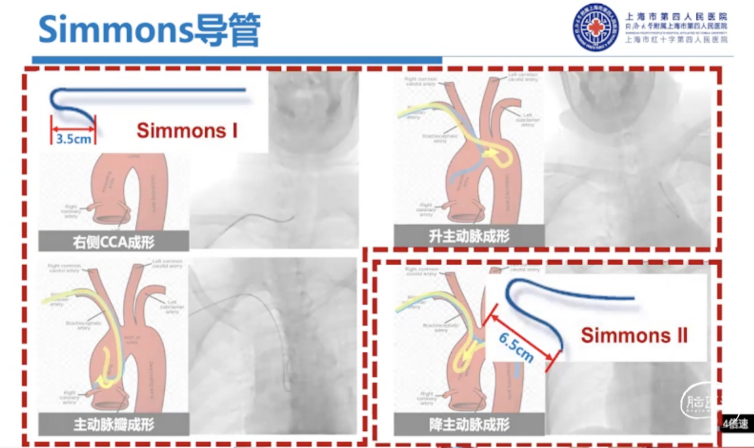

不同Sim导管尺寸对弓上超选也是有影响的,通常在右侧颈总动脉成型、升主动脉成型时更常用Sim I,Sim I头端较短,非常容易通过主动脉弓进入降主动脉。

主动脉瓣成型一般使用较少,但是如果弓型比较特殊,我们使用Sim I导管完成主动脉瓣成型还是非常有效的,对于降主动脉成型以及左侧经桡成形,我们一般会选择Sim II。

器械选择:6F通桥银蛇DA远端通路导引导管/中间导管/长鞘+125cm 5F Sim II导管,这是我们最常用的组合。

选用长鞘的情况下,因为导管较短,有的时候用100cm Sim II配合80cm的长鞘也是可以完成入路建立的,但大部分情况下,我们需要125cm Sim II。在没有现成Sim II中心可用125cm 多功能管手工塑形。